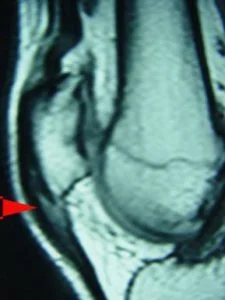

Estudos de imagem para detecção da tendinite patelar joelho

A Ultra-sonografia e ressonância magnética são altamente sensíveis para a detecção de anomalias do tendão em ambos os atletas sintomáticos e assintomáticos. Portanto, um número significativo de resultados falso-positivos pode ocorrer se o médico não realizar a correlação clínico-radiográfica.

Na imagem, a visão lateral do joelho (sagital) de uma ressonância nuclear magnética. A seta vermelha mostra a área esbranquiçada correspondendo à área de degeneração e micro-ruptura do tendão patelar.